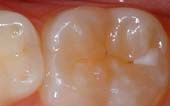

Seal Out Decay

A sealant is a protective coating that is applied to the chewing surfaces (grooves) of the back teeth (premolars and molars), where four out of five cavities in children are found. This sealant acts as a barrier to food, plaque and acid, thus protecting the decay-prone areas of the teeth.

|